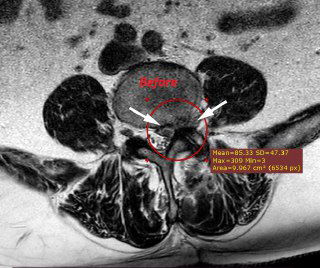

В праздничные выходные пациент самостоятельно выполнил МРТ — выявлены признаки крупного рецидива грыжи.

Особенность случая — парамедианно-фораминальное, с элементами экстрафораминального, расположение грыжи.